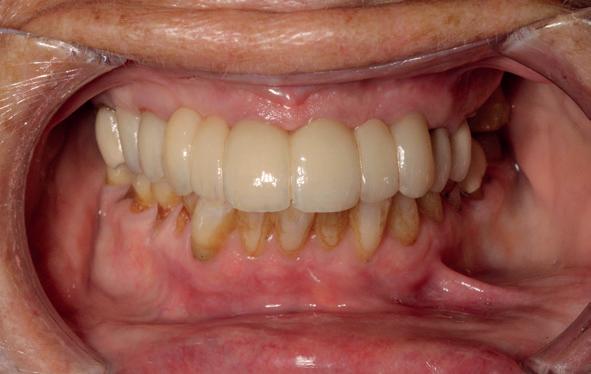

Een patiënt die conventioneel tandheelkundig vrijwel volledig is uitbehandeld, stelt de behandelaar voor complexe keuzes. In dit artikel wordt aan de hand van een uitgebreide casus beschreven hoe diagnostiek, prognosebepaling en interdisciplinair overleg leiden tot een voorspelbaar implantologisch behandeltraject. De casus illustreert hoe een ogenschijnlijk onsamenhangende restauratieve voorgeschiedenis kan uitmonden in een doordacht en succesvol full-arch implantaatgedragen rehabilitatieplan.

In de prothetische fase (zie foto’s) is in de bovenkaak gebruikgemaakt van verschroefde zirconia bruggen, die enkel buccaal zijn opgebakken. Deze bruggen zijn verlijmd op individuele, geanguleerde titanium abutments. In de onderkaak is een verschroefde kunststofbrug op een titaniumbasis (wrap-around) gemaakt. Voor deze combinatie is gekozen vanwege een minder hinderlijk tikkend geluid bij functie en kleinere kans op breuk van de keramiek. Een nadeel is verhoogde slijtage van de kunststof elementen, maar deze zijn in de jaren later eenvoudig te vervangen op de bestaande brug. Ondanks alle digitale mogelijkheden is de afdruk en registratiefase analoog uitgevoerd, omdat in ervaring van de behandelaren dit bij deze totale rehabilitaties op implantaten nog altijd de grootste precisie oplevert. Er is afgedrukt met impregum in individuele lepels en de pasvorm is gecontroleerd met rigide duralay bars. De relatie wordt vastgelegd zoals bij een volledige prothese met waswallen en pijlpuntregistratie. De opstelling in was wordt gepast en laatste correcties worden gemaakt in samenspraak met de patiënt, de restauratieve tandarts en de tandtechnicus. Na het vastzetten van de suprastructuren worden de schroefgaten afgesloten met composiet.

uitgevoerd met restauratief tandarts Paul de Kok, KVPA). 12. Eindresultaat.